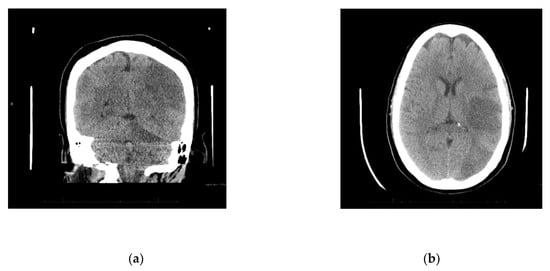

Upon arrival to the new facility, the patient was admitted to the Intensive Care Unit (ICU) and started on a Bumex drip and had a 2D-echocardiogram performed. The echocardiogram demonstrated a positive bubble study in the left atrium, suggesting a patent foramen ovale (PFO), severe pulmonary hypertension with a right ventricular mild dilation and reduced function. During the first three days of admission to the new hospital, the patient developed thrombosis of her right radial artery requiring a radial thrombectomy; she required a transfusion of one unit of packed red blood cells and one unit of platelets, plasmapheresis due to a possible TTP, and a Nicardipine (Cardene) drip. Dry gangrene in the distal right thumb developed due to a right radial artery thrombus (Figure 1b). The patient also demonstrated decreased responsiveness while on sedation vacation. A CT of the brain taken during this time reported multifocal acute infarcts involving the bilateral cerebral hemispheres and the left cerebellar hemisphere, given involvement of multiple vascular territories (Figure 2). A CT arteriogram of the brain and neck with IV contrast demonstrated an incomplete occlusive filling defect of the proximal internal jugular vein, raising concern for a partial thrombosis.

Figure 2.

(a) Diffuse infarcts; (b) Temporal and occipital lobe infarcts.